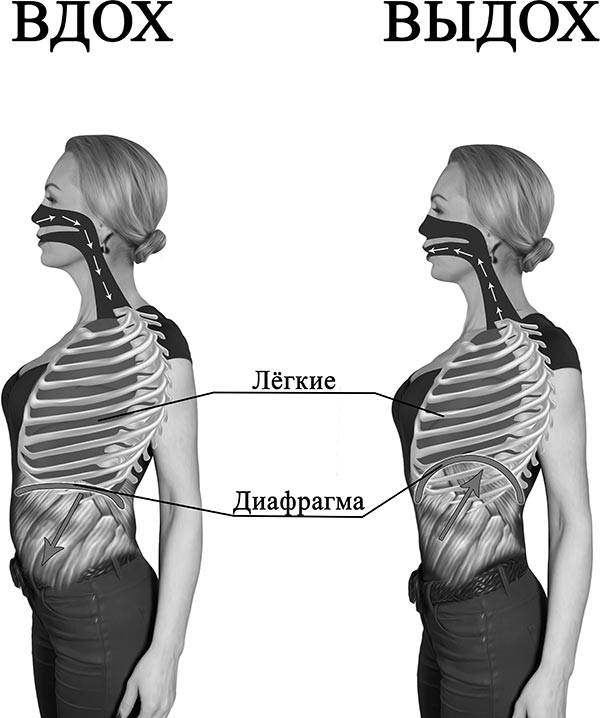

При любом типе дыхания за обработку кислорода отвечают легкие. Но их увеличение, как и изменение объема полости груди, зависит от 2 разных способов:

- При вдохе стенка груди приподнимается и отодвигается от позвоночника, из-за чего полость грудной клетки спереди увеличивается (образуется дополнительный объем между позвоночником и грудиной). В этом процессе участвуют ребра, прикрепленные к позвоночнику под острым углом. Своими концами они формируют дугу, расширяя возможный объем. Так как ребра крепятся к грудной кости, они тянут ее за собой.

- Второй способ зависит от опущения грудобрюшной преграды по направлению книзу. Это – диафрагма, имеющая куполообразную форму. Грудные мышцы отвечают в процессе дыхания за то, чтобы этот купол тянулся вниз, освобождая простор для легких. Середина опускается книзу и создается нужный объем. Из-за опущения грудная часть диафрагмы давит на живот, в результате выпячивается его стенка.

Главный орган в брюшном дыхании — диафрагма. Диафрагмальная мышца — это куполообразная перегородка, она отделяет грудную клетку от органов, расположенных ниже в брюшной полости. На вдохе диафрагмальная мышца идёт вниз и сжимается, заставляя брюшную стенку выдвигаться вперёд. В момент выдоха диафрагмальная мышца возвращается вверх и приобретает форму купола, выгоняя воздух из лёгких.

На вдохе диафрагма движется вниз, на выдохе — поднимается вверх

На вдохе диафрагма движется вниз, на выдохе — поднимается вверх